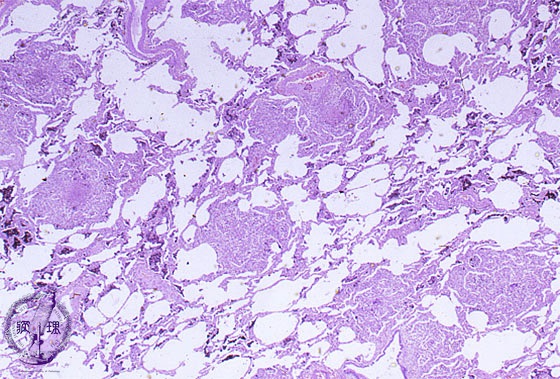

Microscopic view (HE stain, low power view): Disease incorporates uniform granulomatous lesions and spreads via hematogenous dissemination.